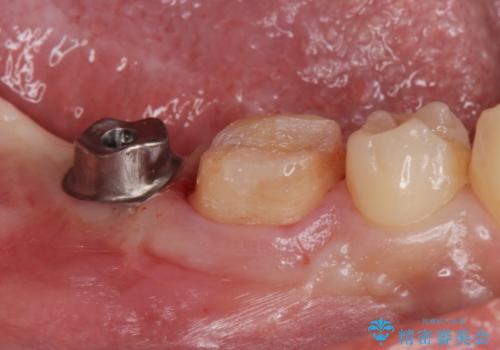

抜歯したところは抜歯後骨の治癒を待ち、CTを撮影しインプラント治療ができる事(骨の厚みなど)確認し治療を行いました。

- ジルコニアクラウン・仮歯 12.1万円 ジルコニアクラウン・インプラント用仮歯 14.3万円 インプラント体 22万円 アバットメント 5万円費用は治療当時の料金となります